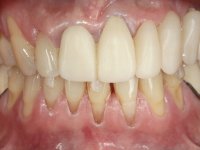

The patient comes to the consultation with a metal-ceramic bridge with great mobility. In addition to the near avulsion of the bridge, the patient was also interested in undergoing fixed oral rehabilitation, which improves aesthetics.

66-year-old male patient, non-smoker. It featured a 5-member metal-ceramic bridge with extreme mobility. Teeth 11 and 21 had infiltrated cervical margins. Both arches showed root exposure with signs of cervical abrasion. Composite resin “slots” were visible on the buccal surfaces of some mandibular teeth compatible with an orthodontic treatment with aligners that the patient was undergoing. After the imaging examination, it was found that the bridge's distal support, tooth 24, was irretrievably lost. The mesial pillars 11 and 21 had endodontic treatment and intraradicular posts. Teeth 25 and 26 also had endodontic treatment and extensive restorations in composite resin. In the lower jaw, two bridges were visible. In the third quadrant a 4-element bridge supported on tooth 35 and on 2 implants placed in the location of teeth 36 and 37. In the fourth quadrant a 3-element bridge supported on tooth 45 and an implant placed in the location of tooth 46. The patient presented a thick gingival phenotype and very good oral hygiene.